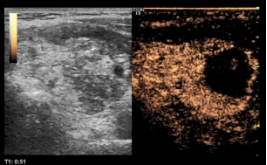

图 术后复查超声及超声造影,超声显示术区及其周围未见出血,甲状腺左叶实性结节呈消融术后改变